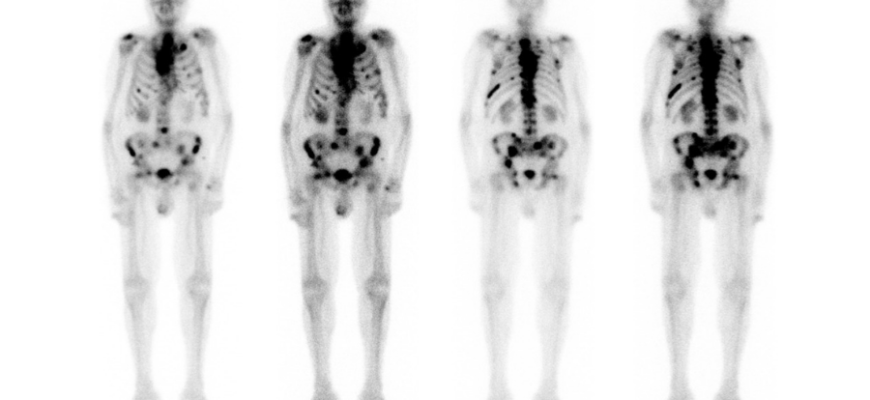

Prostat kanseri en sık olarak kemiklere yayılır. Özellikle omurga, kaburgalar ve leğen kemikleri bu yayılımın en sık görüldüğü bölgelerdir. Hastalık ilerledikçe akciğer, karaciğer ve nadiren beyin gibi organlara da yayılım görülebilir.